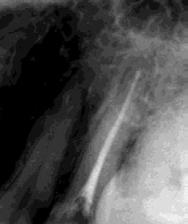

La Figura 14 muestra la imagen del carcinoma epidermoide de la mucosa yugal antes de la radioterapia. La Figura 15 muestra la radiografía dentoalveolar del incisivo central

Osteorradionecrosis de los maxilares: etiología y prevención

superior izquierdo con diagnóstico de necrosis pulpar y un área radiolúcida periapical extensa.

Las Figuras 16 y 17 muestran el tratamiento endodóntico del incisivo central superior izquierdo. Las Figuras 18 y 19 muestran el tratamiento endodóntico del incisivo central superior derecho. Se puede observar que también se realizó la endodoncia del resto radicular del incisivo central superior derecho pues no se debe realizar la exodoncia del mismo.